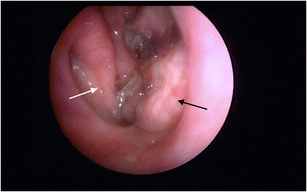

Nasotracheal intubation (NTI) is used for maintaining airway access during maxillofacial surgery or in cases of severe oral trauma. We describe a case of middle turbinectomy complication as a result of NTI. The purposes of this paper are to raise awareness of this complication and review associated imaging findings.

Fig. 1